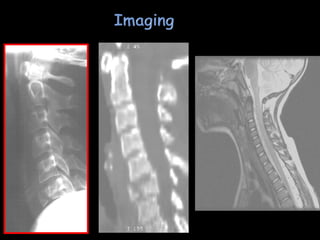

• 34.

 Common mechanismfor central cord injury in elderly—hyperextension with a spondylolytic neck  MRI findings impressive  SCI protocol followed by observation until recovery plateaus  Treatment : same as central cord syndrome.